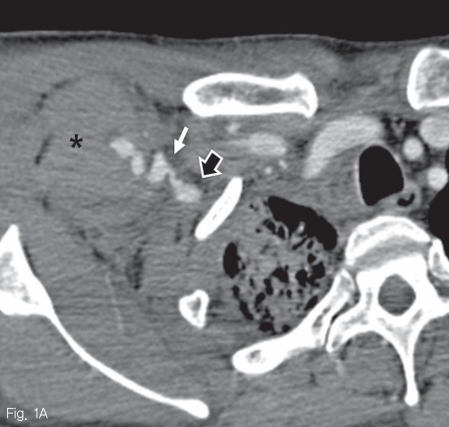

CT 동맥 조영술의 동맥기와 지연기에 우쇄골하동맥 원위부의 전외측에 현성 출혈로 판단되는 조영제의 혈관외유출 및 이로 인한 가성 동맥류가 관찰되었다. 그 주변과 우측 액와부에 걸쳐 많은 양의 혈종이 보였으며, 이로 인해 우측 대흉근이 앞쪽으로 밀려있었다. 또한 이와 인접한 우외측 흉벽의 피부 및 피하부종이 동반되었다 (Fig. 1A, B).

Fig 1A

Contrast enhanced CT angiography A. and maximum intensity projection image B. show active extravasation of contrast media (A, B: white arrows) from anterolateral aspect of right subclavian artery (black arrow, A), forming a large hematoma in the right anterolateral chest wall and axilla (asterik, A)